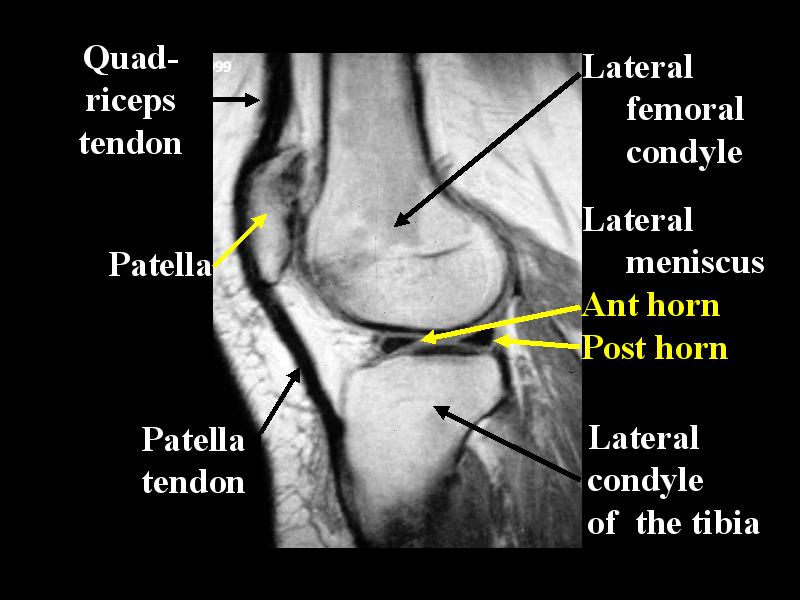

MS 200 MR NORMAL 73